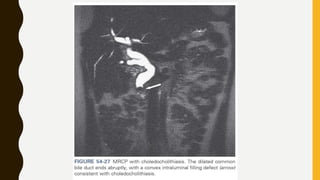

Upper Tract and Lower Tract Imaging for Urothelial Carcinoma

• Urothelial carcinoma of the upper tract can be assessed by an MR urogram (MRU) in

addition to the standard renal mass MRI techniques. MRU can be used in patients for

whom other imaging modalities are contraindicated. MRU is accomplished by using

heavily weighted T2 sequences in which fluid/urine have a high SI on T1-weighted

images with Gd (Chahal et al, 2005). MRU and CTU have the same accuracy in

assessing renal obstruction (Silverman et al, 2009). Nephrolithiasis/calcification on

has no signal characteristics; therefore it appears as a void on imaging. Urothelial

tumors, blood clots, gas, or sloughed renal papilla may exhibit a low signal or signal

voids on T2-weighted images secondary to the high signal of urine (Kawashima et al,

2003).